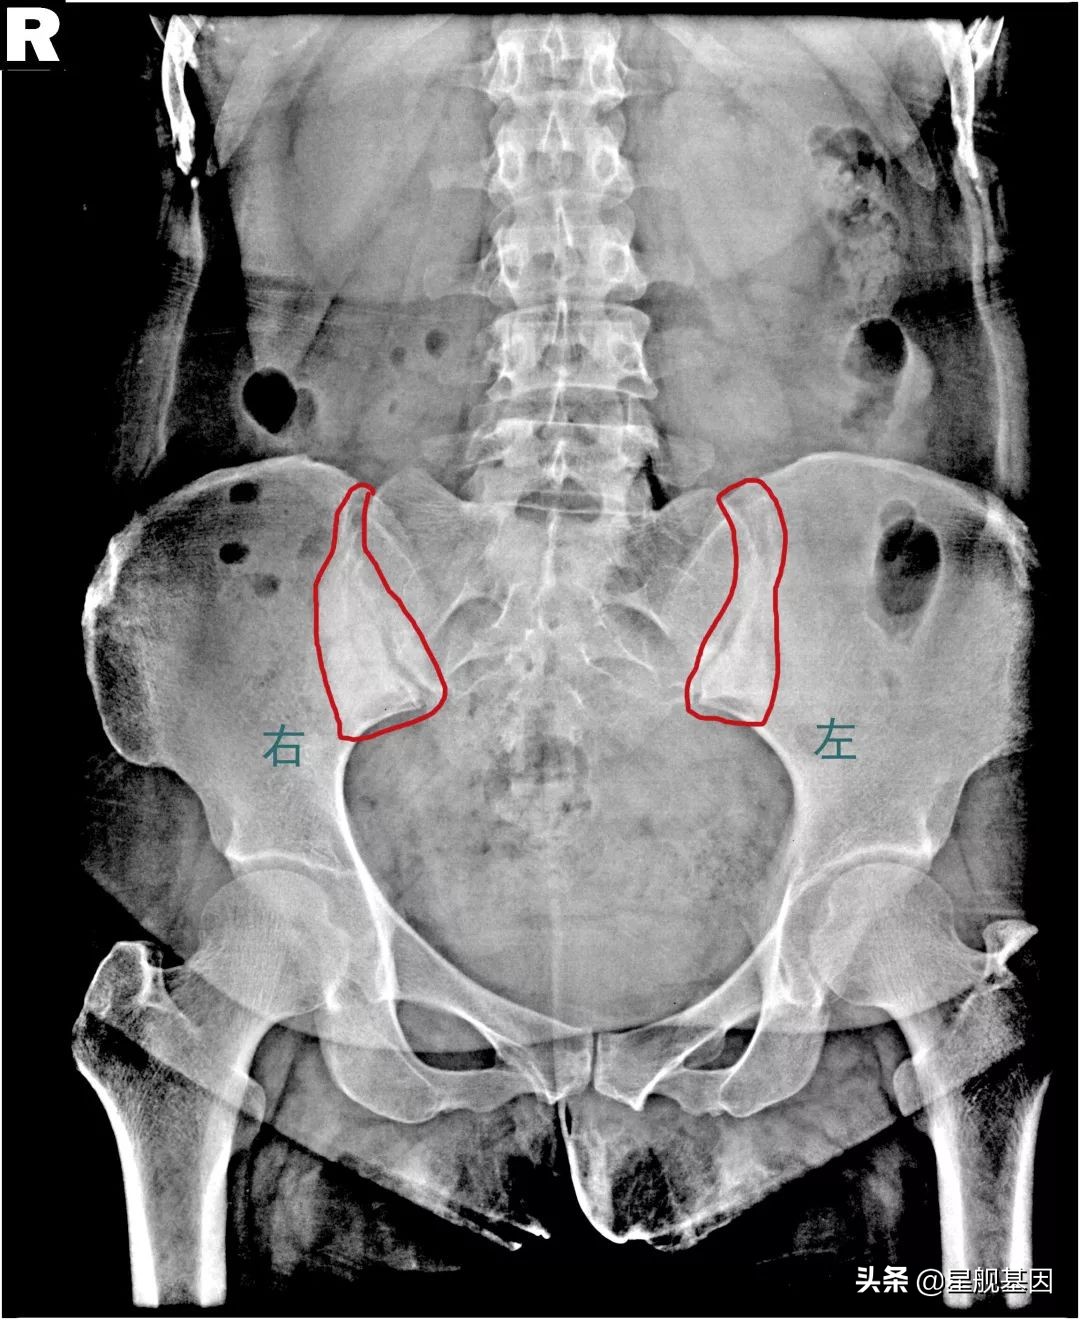

(这是最近一个患者的X光片,典型的双侧髂骨致密性骨炎,个人信息已经隐去)